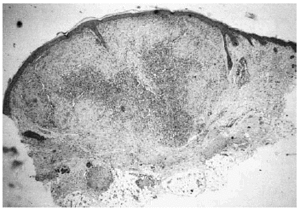

Se realizó biopsia de uno de los tumores que mostró una lesión nodular bien definida, no encapsulada, localizada en la dermis y respetando la epidermis (fig. 2). La parte periférica de la lesión se componía de fascículos compuestos por células fusiformes, de amplio citoplasma eosinófilo y con núcleos alargados. En el centro de la tumoración se encontraban cúmulos de cé-lulas redondeadas o poligonales, con citoplasmas de bordes mal definidos y núcleos hipercromáticos. Esta zona mostraba espacios vasculares con luces interconectadas en un patrón en «asta de ciervo» (fig. 3). La inmunohistoquimia demostró positividad para vimentina y actina específica del músculo. Se practicó hemograma y bioquímica sérica, que fueron normales. La radiografía de tórax, la ecografía abdominal y cardíaca y la tomografía axial computarizada (TAC) cerebral no detectaron anomalías. En la serie ósea se detectaron múltiples imágenes líticas diafisometafisarias en fémures, tibias y húmeros, así como en mandíbula y pelvis, con bordes bien definidos no escleróticos (fig. 4). Se realizó una interconsulta a Neurología solicitando valoración de la parálisis facial, y ésta fue etiquetada de parálisis facial periférica de etiología probablemente obstétrica.

Fig. 2.--Lesión tumoral intradérmica que muestra un patrón bifásico.

Fig. 3.--Detalle histológico. En la parte superior izquierda: patrón hemangiopericitoide. En la parte inferior derecha: patrón leio-miomatoide.